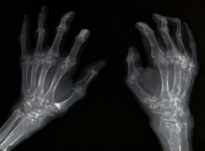

(2)类风湿性关节炎:患者有双手关节畸形,但RF和抗CCP抗体均阴性,不符合该诊断。

全身骨痛是透析相关淀粉样变患者常见的症状之一,其疼痛程度和持续时间因个体差异而异。这种疼痛可能源于β2-MG在骨骼中的沉积,导致骨骼结构的改变和功能的受损。此外,长期的透析治疗也可能导致电解质代谢紊乱、钙磷代谢失调等问题,进一步加剧骨骼疼痛。腕管综合征多为DRA的早期临床表现,主要由β2-MG淀粉样物质沉积于腕管内的腱鞘、滑膜、屈肌腱或屈肌韧带,造成腕管腔相对狭小、腕管压力增高,正中神经受压所致。临床表现为患肢桡侧半手指麻木或刺痛,夜间明显,活动后可减轻;病情严重者大鱼际肌萎缩和功能障碍;屈腕试验,神经叩击试验,或指压试验可阳性。囊性骨损害是DRA最常见的临床骨损害,常发生在腕骨、肱骨头、股骨颈、髋臼、胫骨平台等。囊肿数量和大小随透析龄的延长而增加。囊性骨损害为多发性、对称性软骨下溶骨性改变。淀粉样骨关节病绝大多数发生于滑膜关节附近,并常累及邻近关节囊和韧带,肩关节是最常见的受累部位。破坏性脊柱关节病变主要累及颈椎,是DRA的一种致残性并发症,常为多发性、发展迅速的椎间隙变窄,伴有邻近椎板受侵蚀致骨质破坏。对于出现全身骨痛的患者,医生应高度警惕透析相关淀粉样变的可能性。除了详细的病史询问和体格检查外,还需要进行相关的实验室检查,如血清β2-MG水平的测定,以及影像学检查,如X线、CT或MRI等,以明确是否存在骨骼的病变。